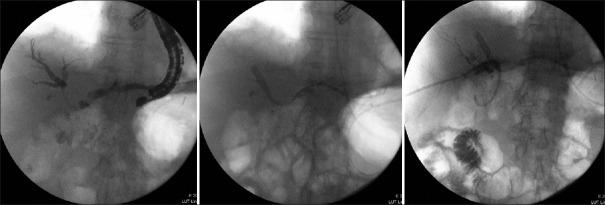

Between January 2015 and September 2018, 20 patients were included. The mean patient age was 68 years. Seven patients had primary liver tumors and 13 had obstructions caused by metastasis. Four patients had Type II stenosis, 7 had Type IIIA, 2 had Type IIIb, and 7 had Type IV stenosis. Sixteen patients underwent EUS-guided hepaticogastrostomy (EUS-HGS) for initial drainage and four as reintervention. For initial drainage, 2 patients underwent EUS-HGS alone and 14 underwent EUS-HGS in combination with another technique: 11 combined with endoscopic retrograde cholangiopancreatography (ERCP), 2 with percutaneous transhepatic drainage, and 1 with ERCP and percutaneous transhepatic drainage. The technical success rate for EUS-HGS in the drainage of MHS was 100%, and the clinical success rate was 95%. The mean percentage of liver drained was 84%, with an average 1.7 endoscopic sessions and an average 2.7 protheses. The early complication rate was 35% and the mortality rate was 5%. Five EUS-HGS/ERCP combination drainage procedures were performed in one session and six were performed in two sessions with similar complication rates and percentages of liver segments drained.

EUS-BD is a feasible and safe technique for initial drainage and for reintervention procedures. The EUS-HGS/ERCP combination seemed to be useful in cases of complex stenosis and could be performed during the same session or in two sessions.